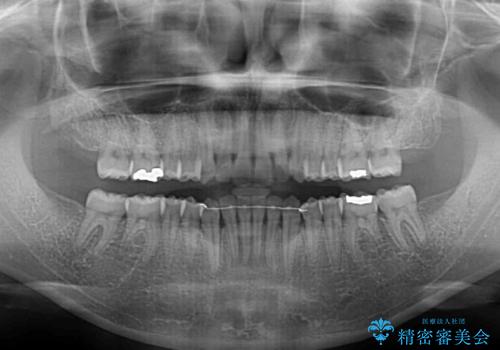

受け口傾向の前歯 すきっ歯の改善

- 前歯の隙間と口元の突出感を気にして来院された患者様です。

嚥下時に舌を突出させる癖があり、成長期に下顎が有意に成長し、歯と歯の間に隙間ができてしまいました。

舌の癖を改善し、インビザラインにて治療を行うこととしました。

舌癖を改善したことで、隙間や突出感を改善することができました。

隙間は後戻りしやすいため、舌側を細いワイヤーで固定することとしました。